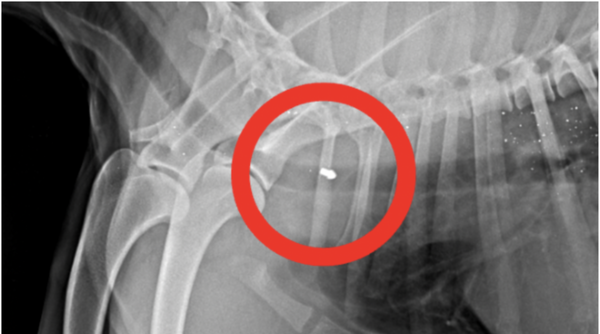

Stop the Shooting of Dogs in Bahrain!